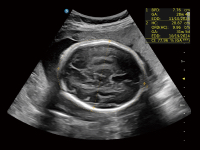

作为开立医疗全新打造的超高端旗舰超声产品,从探头抬起唤醒开启扫查到多维探头发射接收,通过先进的场成像发射、自适应聚合重建等技术,基于RF Data原始射频数据在图像生成、高端功能等方面实现突破,为妇产科、儿科提供全方位临床解决方案。

梦溪®P80以“关爱女性”为基石,提供全方位的解决方案,量身定制以满足女性的健康需求,涵盖妇科、生殖健康检查、产前筛查及产后康复等领域。